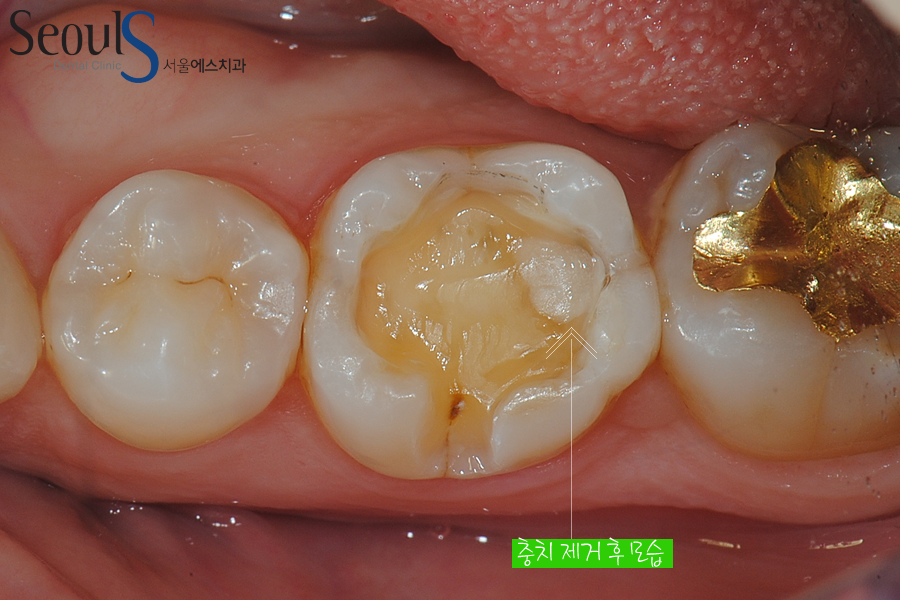

충치를 깔끔하게 제거했습니다

빈 공간이 보이는데 인레이 제작 후 때워 치료를 마칠 예정입니다